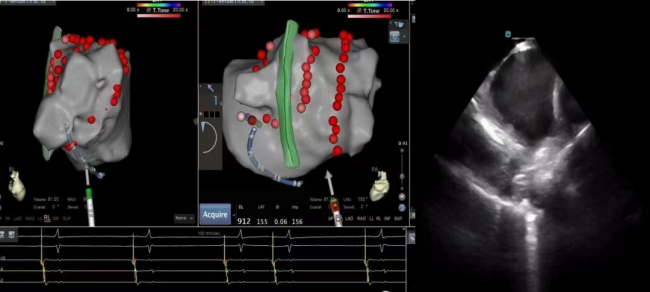

68岁的张先生,因“阵发性房颤、阵发性房扑”就诊于心血管内科,完善相关检查提示心房颤动、心房扑动伴不固定型房室传导阻滞,非特异性ST段异常,具射频消融治疗指征,心血管内科团队经过缜密的术前讨论、方案制定,与患者及家属充分知情沟通后,成功实施ICE辅助下室早导管射频消融术。术后患者恢复窦性心率,未诉特殊不适。香港马会app心血管内科主任、主任医师蒋路平介绍,心腔内超声心动图(ICE)就像是心内科介入医生的“透视眼”,它是指在导管的顶端安置超清超声探头,经外周血管输送至心腔内部,对心脏及其邻近组织进行实时高质量成像和血流动力学测定的超声成像技术,犹如在心脏里长了一双明亮的眼睛一样,可以直观地观察心腔内结构,更清晰、精确定位完成手术,是各种心脏介入手术中重要的辅助工具。该项技术能更直观地显示心腔内结构及实时导管位置,有助于术者更精准快速地进行标测,显著提高了消融的成功率及安全性,减少了手术并发症,缩短了手术时间。心腔内超声心动图(ICE)还能有效运用在“左心耳”封堵术,避免患者术前全麻下食道超声的痛苦,及并发症发生,减少手术费用。

一些需要精准定位的特殊心律失常(如乳头肌室性早搏、希氏束旁室性早搏),通过ICE可以更快更便捷的进行解剖标测。三维心腔内超声能精准定位目标靶点,消融有的放矢,避免累及其他重要结构。

在左心耳封堵手术中,ICE可辅助穿刺,提高封堵手术效率。使封堵器多角度灵活到位,对左心耳开口大小精确测量并进一步释放封堵器,全程可视,提高手术效率,同时降低射线量。对于卵圆孔未闭患者,通过心腔内超声,可直视“隧道”,卵圆孔未闭区清晰可见,封堵器释放过程全程可视,绿色安全。